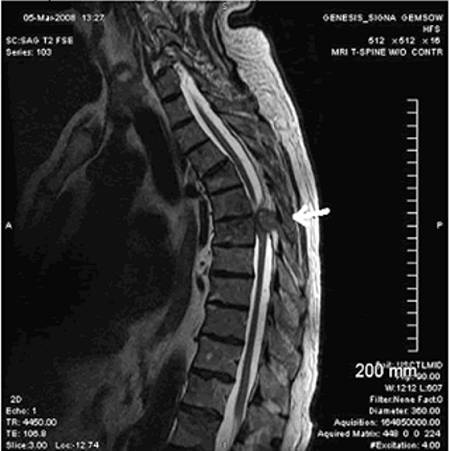

- Исследование на магнитно-резонансном томографе может дать полную и подробную картину о проблемах позвоночника. Прибор представит снимок в любой плоскости.Он может сделать срезы с небольшим шагом, если нужно уточнить и расширить зону обследования. В числе важных преимуществ этого метода — не имеет вредного излучения.

- Редко для изучения проблемы применяют компьютерную диагностику. Она может показать какая ситуация в обследованной зоне, только придётся использовать контрастное вещество. Это обстоятельство создаёт в некоторой степени возможность осложнений для пациента.

- Миелография — способ увидеть область патологического процесса путем введения рентгеноконтрастного вещества в эпидуральное пространство позвоночного столба. В сочетании с КТ используется как альтернатива, если МРТ противопоказано.